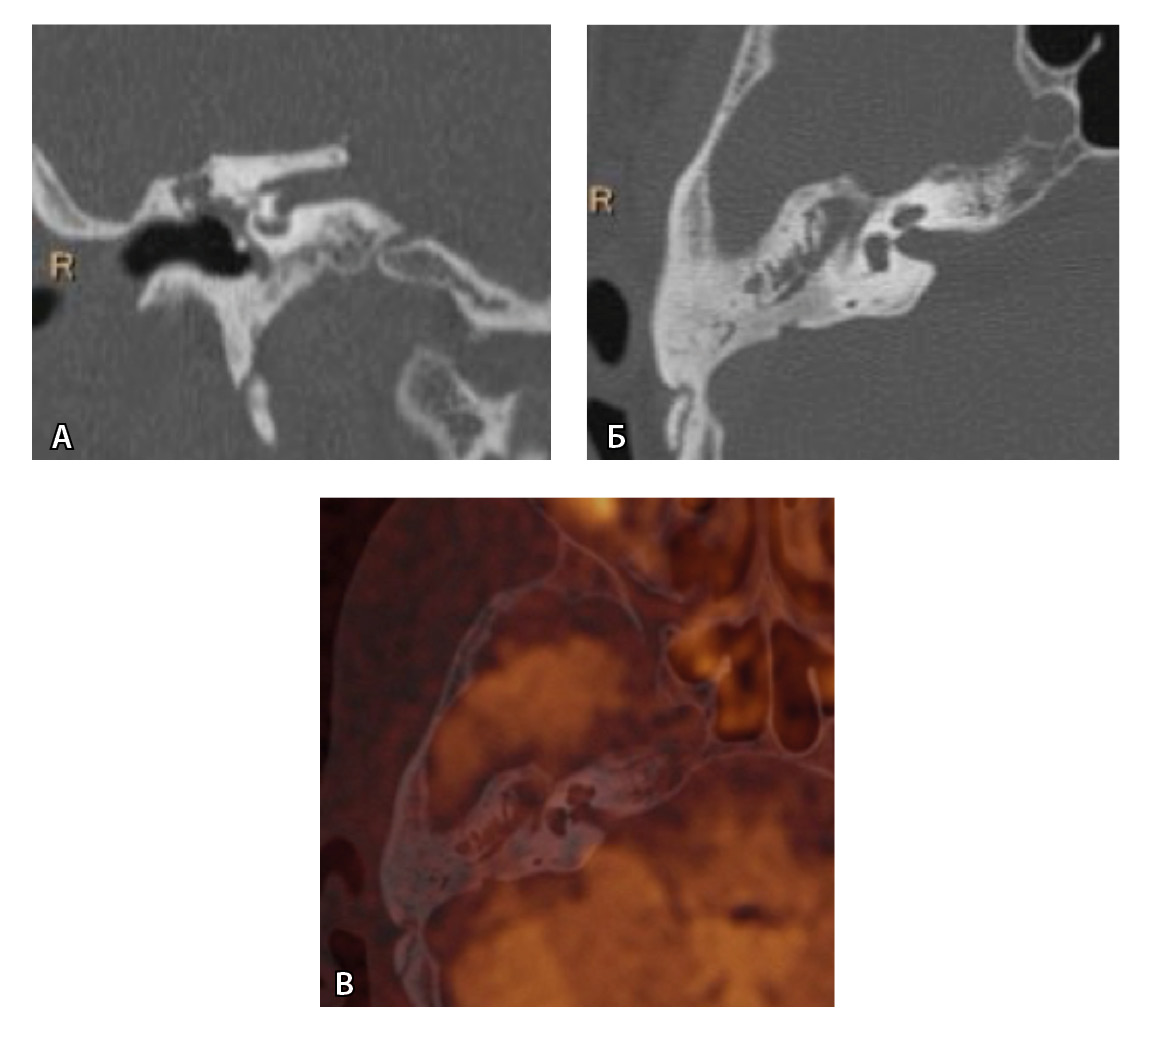

Одним из интересных встреченных нами случаев ложноположительных МР-результатов было грибковое поражение послеоперационной полости с отрицательной динамикой в течение 16 месяцев (рис. 5).

Рис. 5. При первичном послеоперационном исследовании на Т2-взвешенных изображениях во фронтальной плоскости определяется пневматизированная послеоперационная полость (А), без признаков ограничения магнитно-резонансной диффузии (Б). При контрольном исследовании – отрицательная динамика с появлением пристеночных разрастаний вдоль стенок послеоперационной полости (В), ограничивающих магнитно-резонансную диффузию (Г). Данные интерпретированы как рецидив холестеатомы. При оперативном лечении и последующей гистологии – грибковое поражение среднего уха